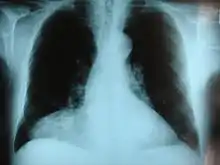

| Morgagni hernia seen on a chest radiograph. | |

This rare anterior defect of the diaphragm is variably referred to as a Morgagni, retrosternal, or parasternal hernia. Accounting for approximately 2% of all CDH cases, it is characterized by herniation through the foramina of Morgagni which are located immediately adjacent and posterior to the xiphoid process of the sternum.[4]